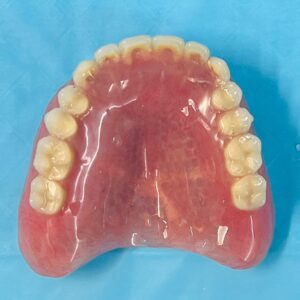

There are two types of implant dentures: bar-retained and ball-retained. In both cases, the denture will be made of an acrylic base that will look like gums. Porcelain or acrylic teeth that look like natural teeth are attached to the base. Both types of dentures need at least two implants for support.

Upper Jaw Implant Complete Dentures

Upper Jaw Implant Overdentures on 3 Implants